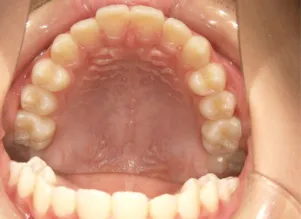

治療後⑩高2:17y7m 抜歯治療終了

口元の治療前後:15y5m→17y7m スッキリしました